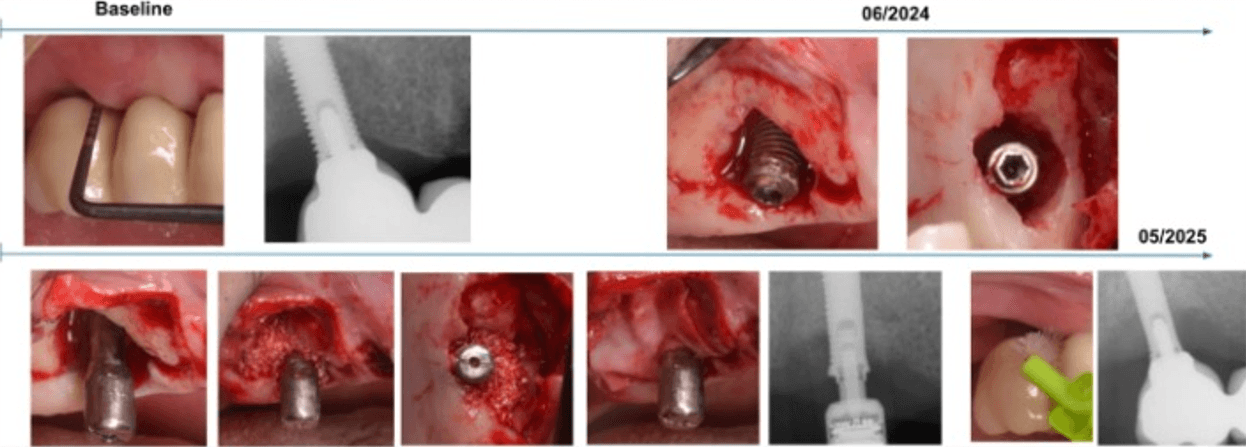

This case involved a patient diagnosed with inflammatory environment, treated in June 2024.

The surgical procedure included implantoplasty and guided bone regeneration, followed by the immediate placement of the MAGDENT Miniaturized Electromagnetic Device (MED) for a duration of 3 weeks. At the 3-week mark, after soft tissue stabilization, the final prosthesis was delivered.

The clinical outcome shown here represents a follow-up at 11 months (approximately 1 year) post-treatment. The site demonstrated excellent tissue healing, absence of inflammation, and radiographic bone stability, supporting the role of PEMF technology as a complementary approach in managing peri-implant defects.

This case, performed by Prof. Alberto Monje, involved a patient diagnosed with inflammatory environment, presenting with advanced bone loss and bleeding on probing. The treatment followed a surgical regenerative protocol combining mechanical decontamination and biological stimulation using the MAGDENT Miniaturized Electromagnetic Device (MED). The procedure included implantoplasty, thorough surface debridement and decontamination, and guided bone regeneration (GBR) with a particulate bone graft and collagen membrane to restore the lost peri-implant bone structure. Immediately after the regenerative procedure, the MED healing abutment was connected to the implant and left in place for three weeks, delivering continuous pulsed electromagnetic field (PEMF) stimulation to promote cellular activation, angiogenesis, and bone remodeling at the defect site.

After soft tissue stabilization, the prosthesis was reinstalled, and long-term follow-up at 11 months demonstrated excellent clinical and radiographic outcomes. The treated site exhibited complete mucosal healing, absence of inflammation or pocketing, and stable bone regeneration with clear re-establishment of crestal bone levels around the implant. Radiographs confirmed maintenance of the regenerated bone volume and implant stability, while clinical evaluation showed healthy peri-implant tissues with ideal color, tone, and contour.

• This case highlights the effectiveness of the surgical inflammatory environment management protocol integrating PEMF technology, showing how the MED device can enhance bone regeneration and accelerate healing when combined with conventional regenerative techniques such as implantoplasty and GBR. The synergy between surgical decontamination and electromagnetic stimulation supports a predictable, biologically driven regeneration in peri-implant defects, offering a viable alternative to more invasive resection procedures.